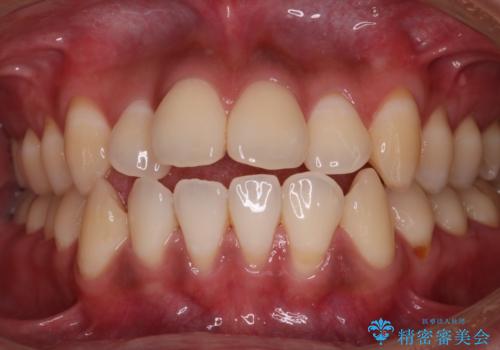

- 出っぱによる口元の閉じにくさを主訴に来院されました。上顎の出っ歯と上下顎叢生も認められたため、上下顎両側4番抜歯を行い、ワイヤー矯正で治療する治療計画を立てました。

上顎にはMI(マイクロインプラント)を埋入して固定源とすることで出っ歯の改善を図りました。